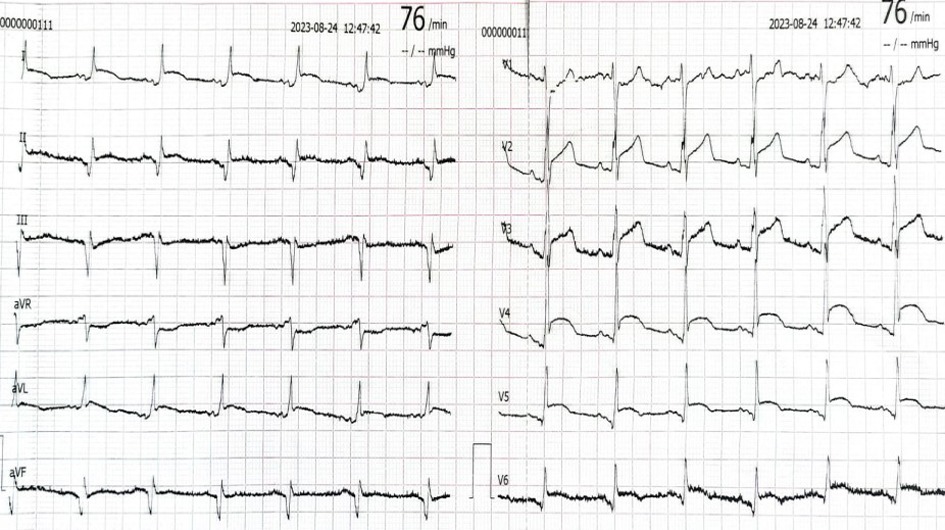

Li YM, Jia YH, Tsauo JY, et al. Case report: ST-segment elevation in a man with acute pericarditis[J]. Front Cardiovasc Med, 2020, 7:609691.doi: 10.3389/fcvm.2020.609691.